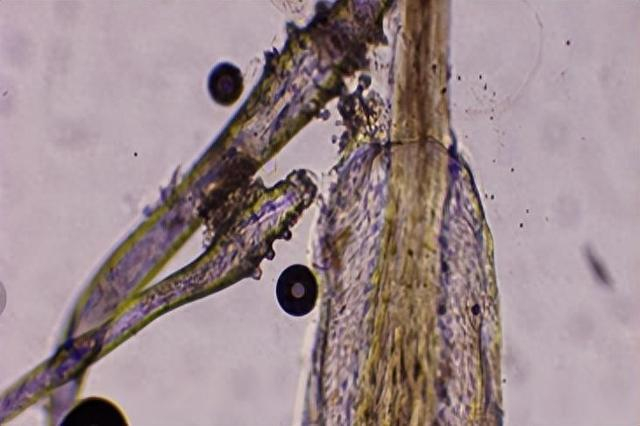

“眼睛反复发痒,一直以为是过敏,滴了眼药水也时好时坏,没想到竟是睫毛上长了螨虫!”王女士在浙江省人民医院眼科中心就诊时,看着检查屏幕上睫毛上附着的螨虫,既惊讶又困惑。

王女士告诉医生,之前她为了提升颜值,前往一家美睫店种睫毛,此后便频繁出现眼部瘙痒症状,每次发作都自行购买眼药水缓解,却始终未能根治。直到近期症状加重,才专程前往医院就诊,没想到竟是螨虫感染,继而引发了睑缘炎。

浙江省人民医院眼科中心专家陈亦棋表示,近期随着新春美睫需求的激增,类似王女士这样的病例明显增多。“眼睑周围皮肤薄弱,毛囊和皮脂腺丰富,本身就是螨虫喜好的生存环境。”陈亦棋进一步解释,种睫毛过程中,假睫毛、嫁接胶水、镊子、剪刀等器械若未经过严格消毒,螨虫极易附着其上,在操作时侵入眼睑毛囊及睑缘部位,进而引发睑缘炎、结膜炎、角膜炎等一系列眼部问题。